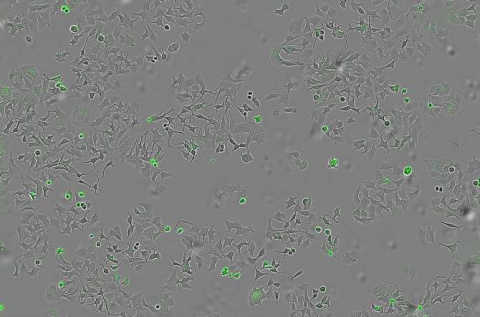

Dos imágenes de microscopía de fluorescencia basada en hoja de luz de cerebro de ratón. En cada caso, se analizó el cerebro para ver la cantidad de acumulación de placas Aβ. En color rojo: placas Aβ. En verde: vasos sanguíneos de la barrera hematoencefálica. A la izquierda: 12 horas después de NO haber sido tratado con nanopartículas. A la derecha: 12 horas después de haber sido tratado con nanopartículas. (Imágenes: IBEC)